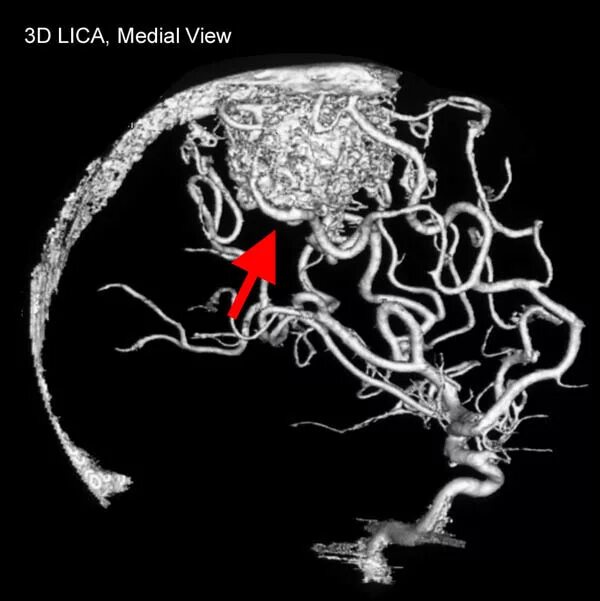

Мальформация сосудов